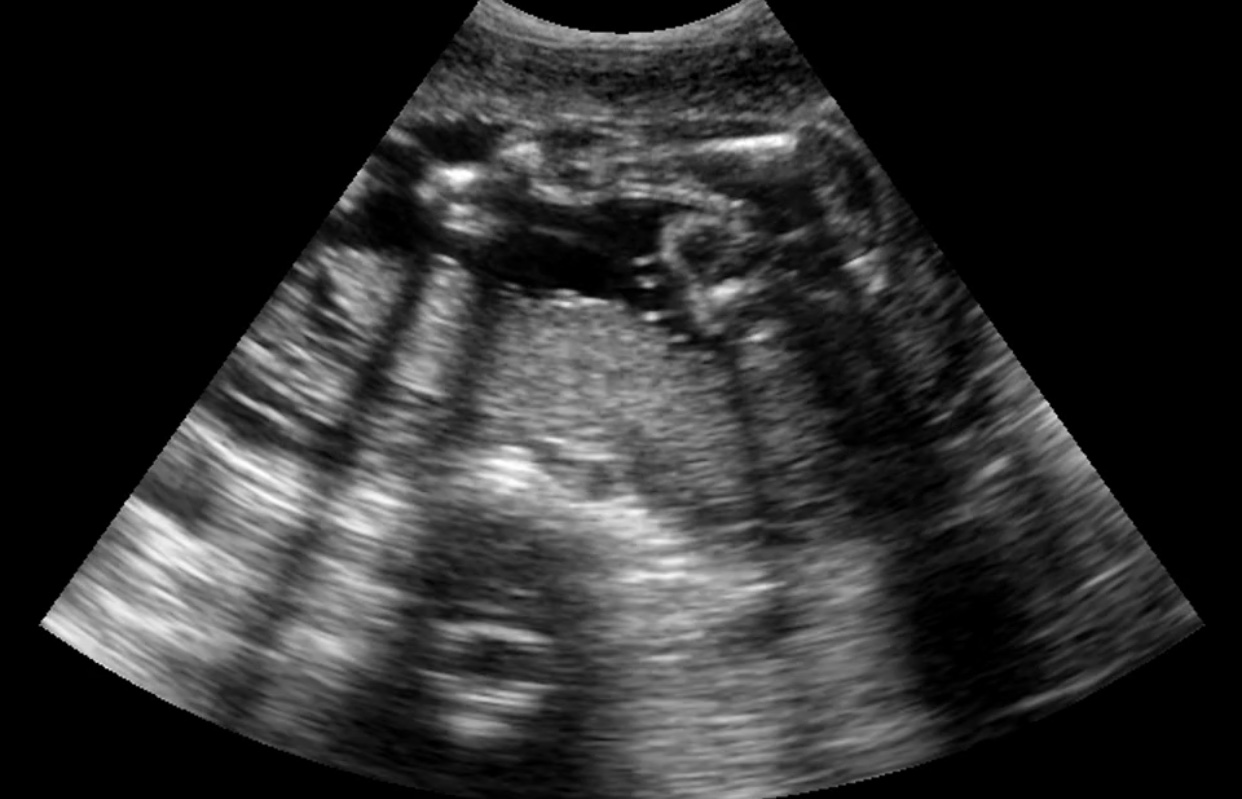

Thank you ladies also have these potty shots plus my 12 weeks scan Attachment 42584

I’m Leaning towards a girl!

Girl from potty shot

girl

Been confirmed a girl 💝💝💝 would you guys say definitely a girl ?xx

Looks girly to me.